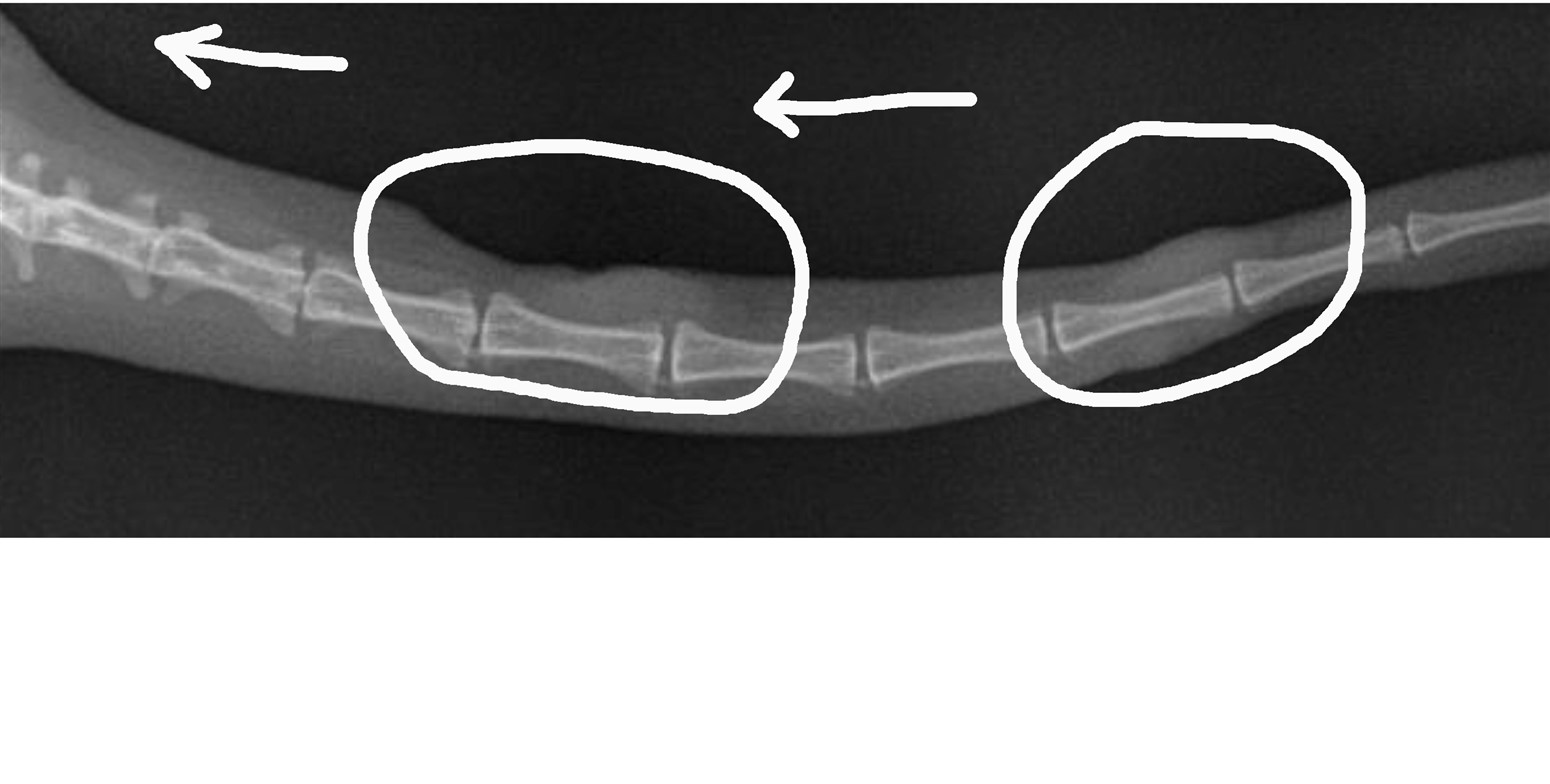

Diagnosis is based on fungal detection by cytology which, as in all the cases shown above, was made immediately on first consultation. Rapid further investigation was recommended to include imaging (dedicated dermatological histopathology with ultrasound, radiography and/or CT). Fresh frozen tissue sampling, during these initial investigation, then allowed subsequent specialised culture to provide definitive diagnosis and species identification. This allowed more definitive surgical and medical treatment alongside more informed prediction of prognosis.

Treatment often involves surgical excision, or amputation if possible, in cases of localised skin disease followed by systemic antifungal therapy, with agent of first choice depending on all important culture results. Relapses after treatment are common especially when diagnosis was delayed. The prognosis is guarded to poor in cats with multiple lesions and systemic or neurological involvement.